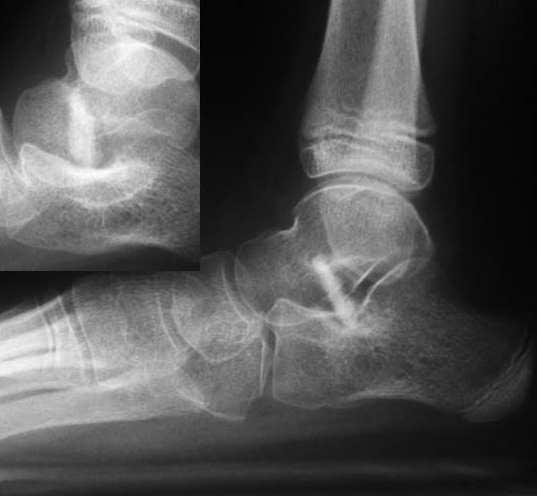

• Röntgenkontrolle (Bild 21,22).

• Röntgen des dargestellten Falles 3 Monate post OP (Bild 25,26)